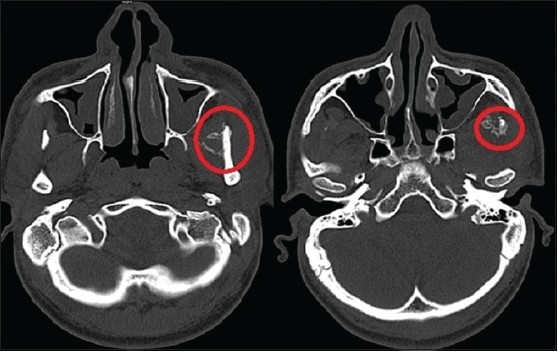

Olha, como tudo que é raro, ninguém pensa neste diagnóstico de primeira, o que pode tornar um desafio para o clínico. Como escrevi trismo é o sinal característico. Deve se observar histórico de trauma, cirurgia ou injeção no local. radiografia panorâmica não ajuda muito pela sobreposição de imagens. Assim, tomografia computadorizada é o exame de imagem necessário para diagnóstico e planejamento cirúrgico.

A imagem é bem circunscrita, bem atenuada perifericamente e menos no centro. Dependendo da maturidade da MO algumas lesões podem estar ou não atreladas a imagem principal.

A figura veio deste caso: Reddy SD, Prakash AP, Keerthi M, Rao BJ. Myositis ossificans traumatica of temporalis and medial pterygoid muscle. J Oral Maxillofac Pathol 2014;18:271-5